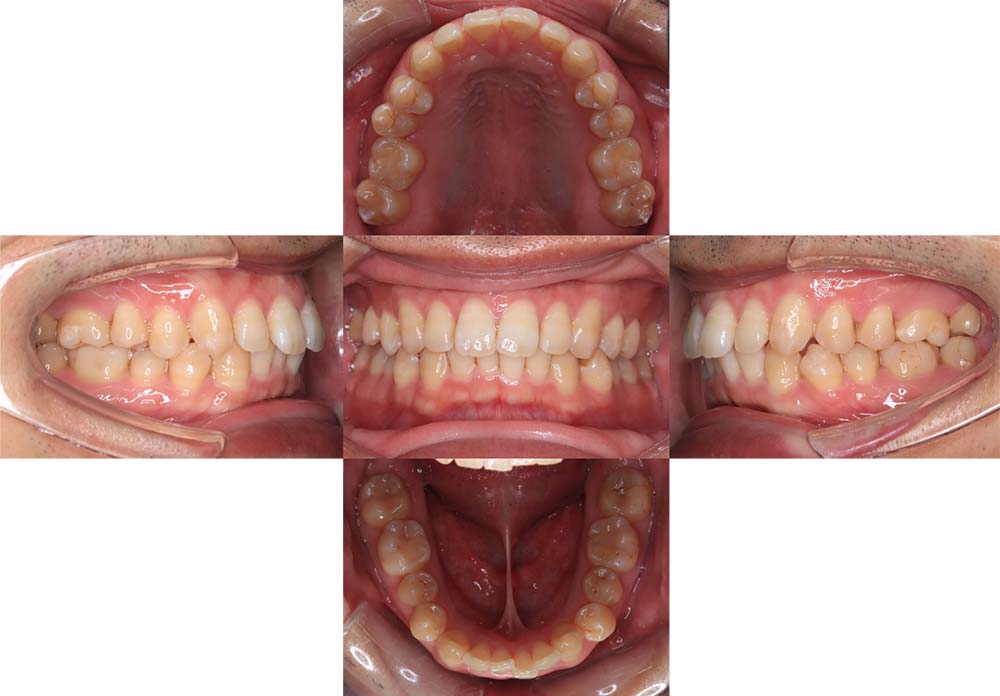

症例03

| 主訴 | 歯並びがガタガタしている。 |

| 診断名あるいは主な症状 | 過蓋咬合、叢生 |

| 年齢/性別 | 26歳・女性 |

| 矯正ステージ | 大人の矯正治療 |

| 治療方法 |

ワイヤー矯正 歯科矯正用アンカースクリュー(3本) |

| 抜歯部位/抜歯有無 | 抜歯 |

| 治療内容 | 上下顎の奥歯を後方に移動後、ガタガタの改善と上下顎前歯を後退させた。 |

| 費用 |

90万円程度(2025.10時点の料金となります。) ※矯正基本料金、アンカースクリュー、審美ブラケットを含む |

| 治療期間 | 2年8ヶ月 |

| 主なリスク・副作用 | 痛み、歯根吸収、歯肉退縮、虫歯、後戻り |